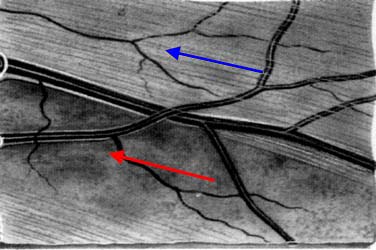

Modrá šipka - ukazuje plochu na sítnici, která obsahuje nervová vlákna. Sítnice je jemně proužkovaná, světlejší, cévy "jsou jako pod závojem". Červená šipka - ukazuje místo bez nervových vláken. Sítnice je tmavší, bez proužkování. Cévy jsou ohraničeny neobvykle ostře.